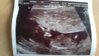

jestem sorki ale usg było na 13 i zanim do domu dotarlam. wszystko jest okej, dzidzia zywa rusza się tańczy, wkladala raczki do buzi caly czas. wynik NT to 1.2 a dopuszczalne jest do 2.5 a wiec na usg nie wygląda żeby był obciążony jakimis chorobami, no ale ostatecznie dowiem się później, z reszta wy już to wiecie. Tak bym chciała już oddechnac, ale ciagle się boje.

Załączniki

• DSC_0612.jpg

DSC_0612.jpg

23,6 KB · Wyświetleń: 64